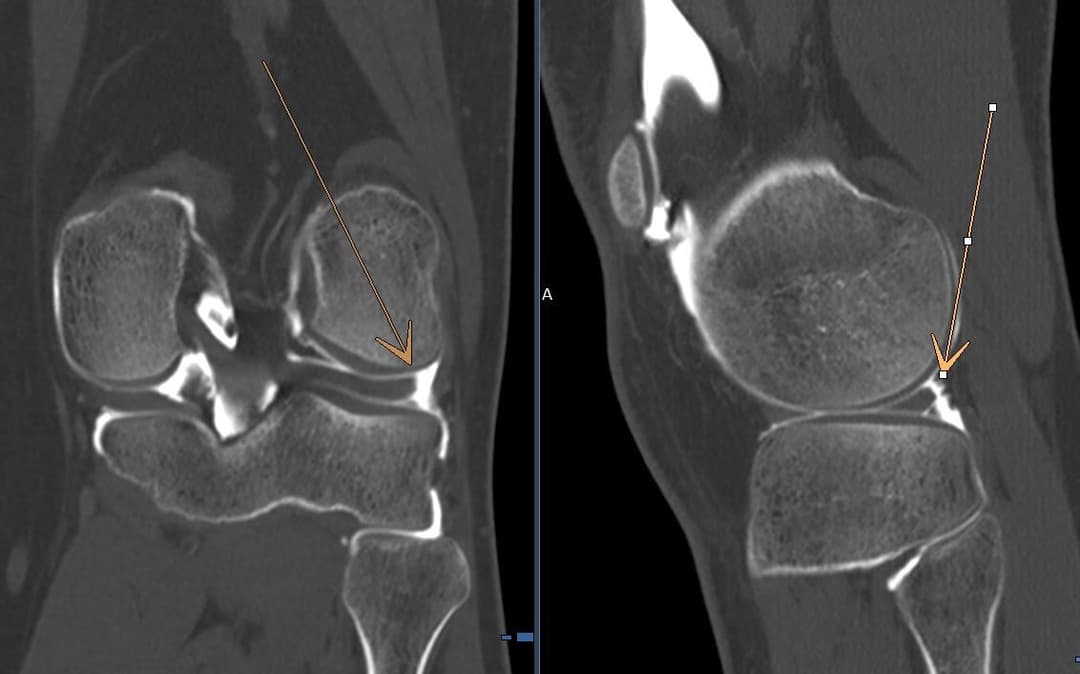

Désinsertion capsulo méniscale latérale

Composante fissuraire oblique grade 3 du segment postérieur du

ménisque latéral, proche du mur méniscal atteignant la surface articulaire inférieure et le mur méniscal.

Extension de la lésion avec rupture partielle des attaches méniscales postérieures et aspect de désinsertion capsulo-méniscale partielle sur le versant postéro-latéral du ménisque latéral.